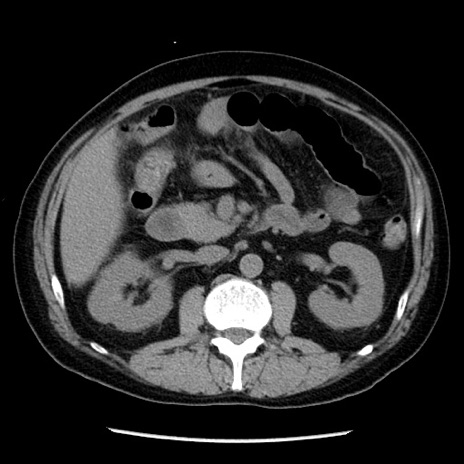

症例29(横断像)

【症例】40歳代男性

【現病歴】2日前から胃痛あり。徐々に周期的な激痛に変化した。本日になっても激痛があるため受診。

【身体所見】意識清明、BT 38-39℃台あり、腹部:膨満、やや硬、右下腹部に圧痛あり。

【データ】WBC 8500、CRP 23.26